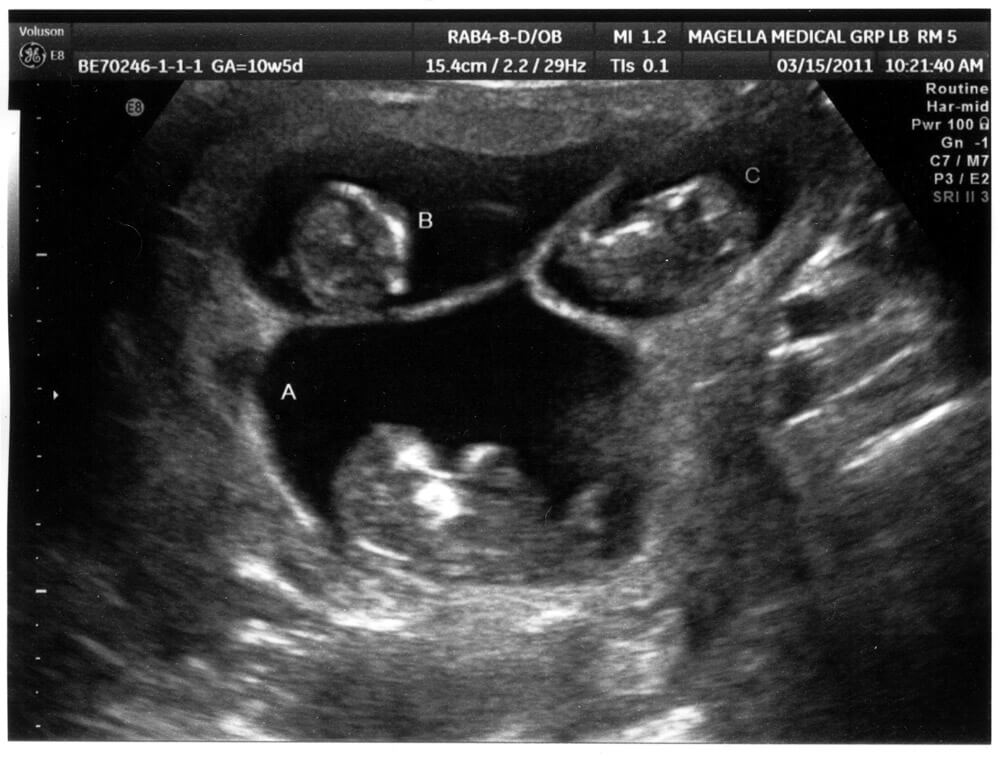

Sarah and Andy Justice were thrilled upon hearing the news they were chosen by a third birth mom. They were so thrilled, in fact, that they were there for her every step of the way. The birth mother even invited them to an ultrasound appointment.

At the ultrasound appointment, Sarah and Andy would have a chance to see their new child for the first time. However, something strange showed up on the scan that displayed on the ultrasound monitor. Everything looked normal for the birth mom, but to her surprise and everyone else's, she was actually carrying three babies instead of one!

Sarah, Andy, and their birth mother were completely shocked to see three heartbeats on the ultrasound monitor. They have worked so hard for so long just to be blessed with one bundle of joy, but now the universe was giving them three.